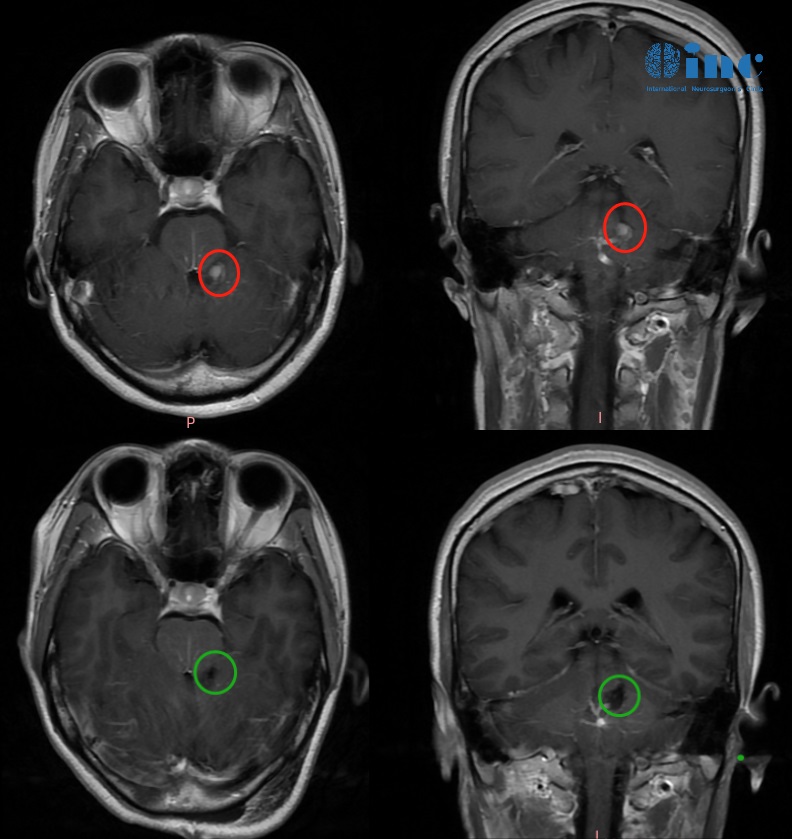

圖:不同位置的腦膜瘤